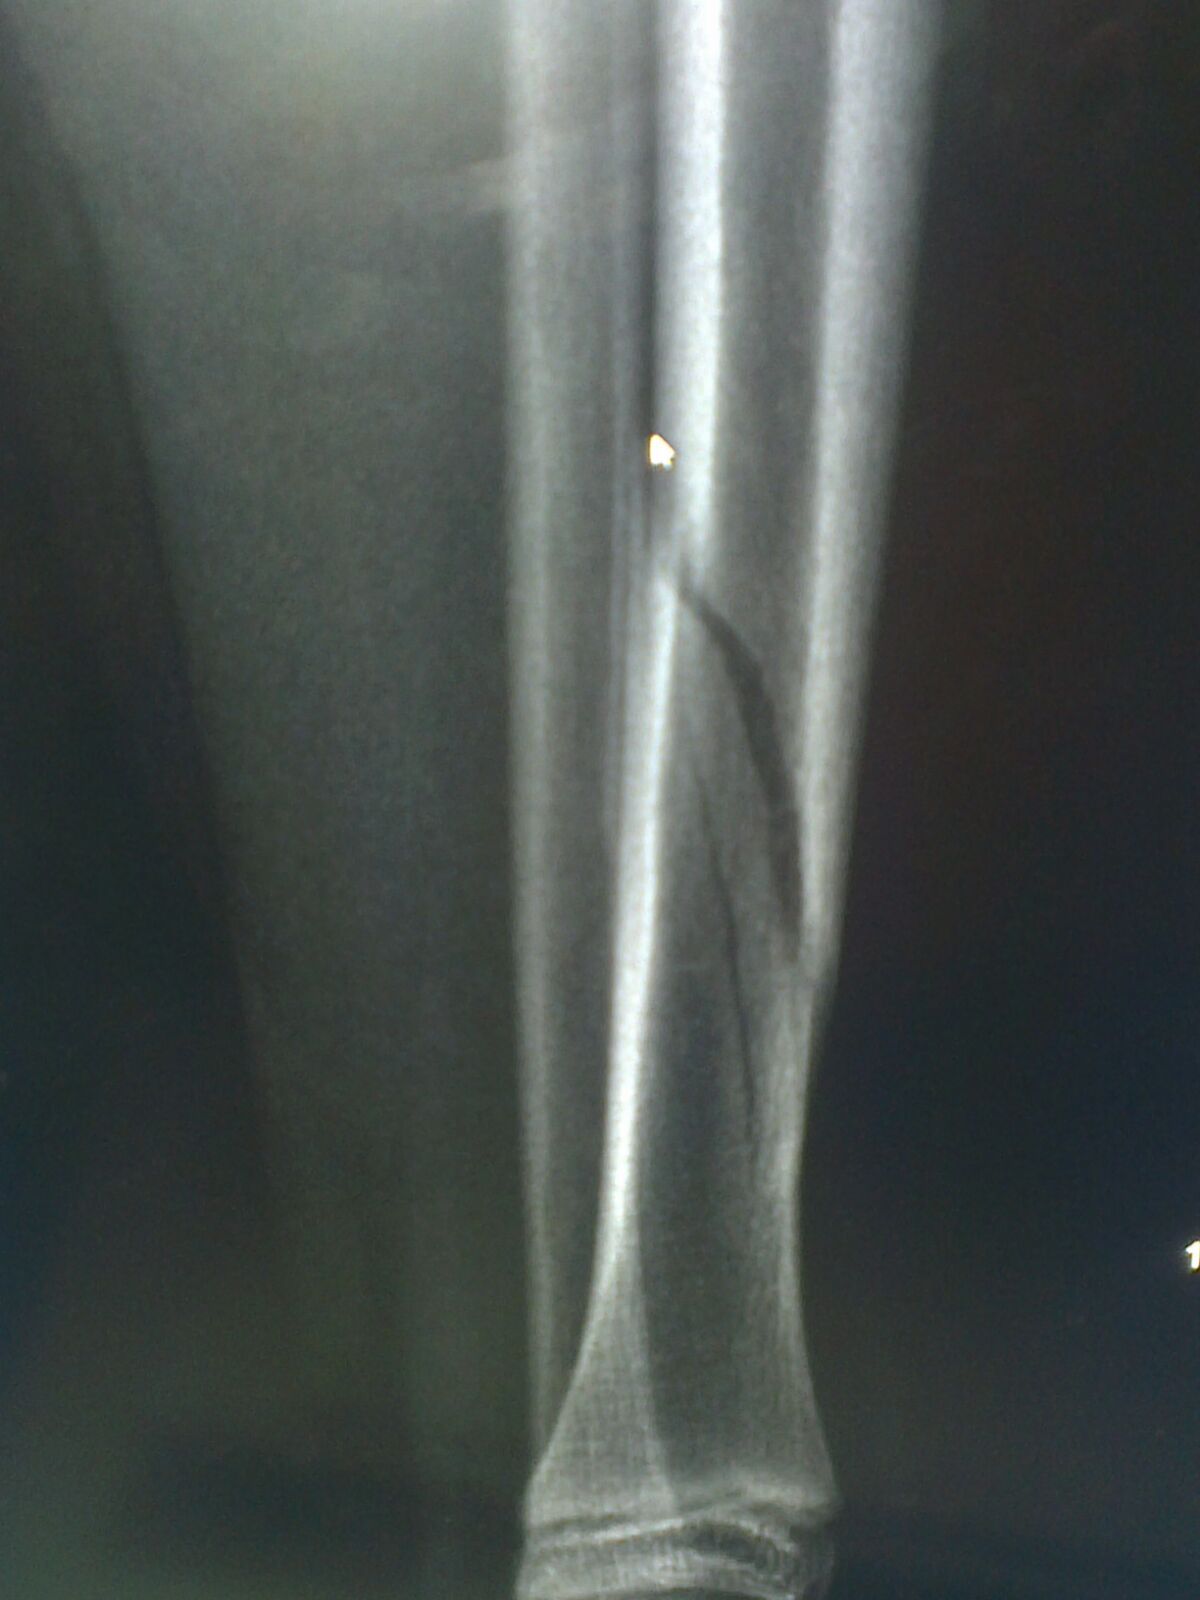

Emilia – Spiralschienenbeinbruch 04.09.2015 um 18:00 5. September 2015 fpuetz — — Von WhatsApp gesendet Uncategorized